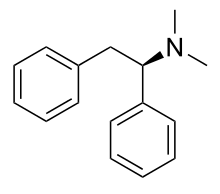

Diphenylmethylpiperazines